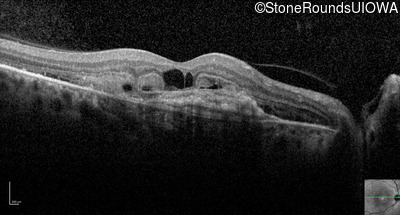

Visit at age: 59 years

Optical Coherence Tomography - Right - 20/200 +1

Exemplar / OCT Stack